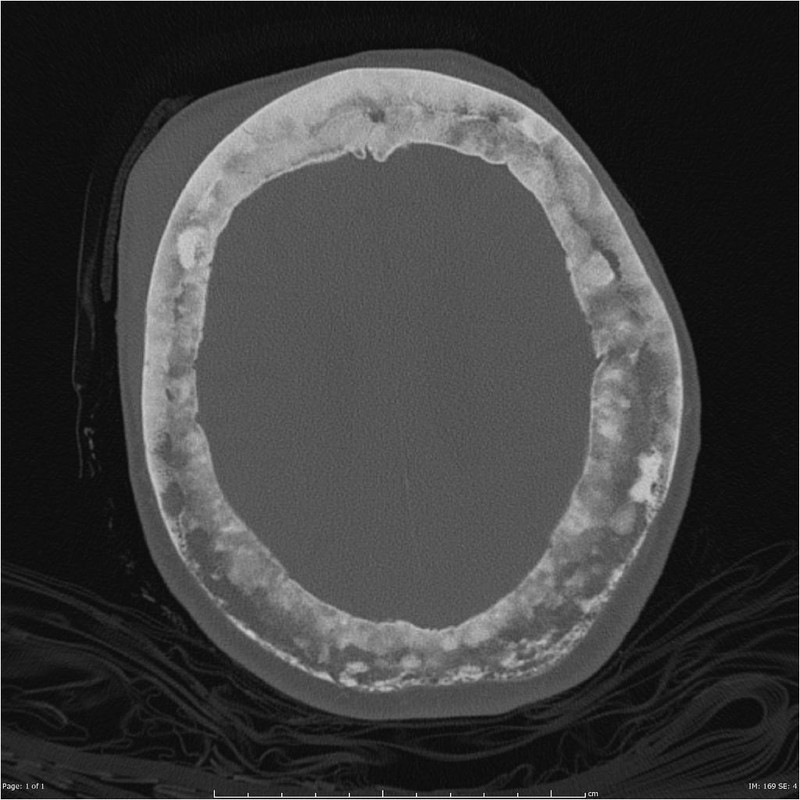

paget disease of bone

A 72-year-old man presents for a routine follow-up in his general practitioner's office regarding his type 2 diabetes and hypertension management. He reports feeling generally well, with no specific complaints of bone pain, fractures, or changes in his hat size. His past medical history includes well-controlled type 2 diabetes mellitus, essential hypertension, and obesity. He denies any recent falls or trauma.During the visit, his vital signs are stable: temperature 36.80C, blood pressure 130/80 mmHg, pulse 70/min, respirations 16/min, and oxygen saturation 98% on room air. Physical examination is unremarkable, with no bony tenderness or deformities noted. Routine laboratory tests ordered during his visit reveal several abnormal findings.Given the patient's presentation and laboratory findings, what is the most likely diagnosis and the initial management strategy?